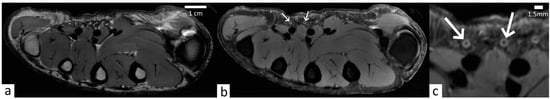

3. Results

3.1. Quality Assurance

3.2. Nerve Description

3.3. Pacini Description